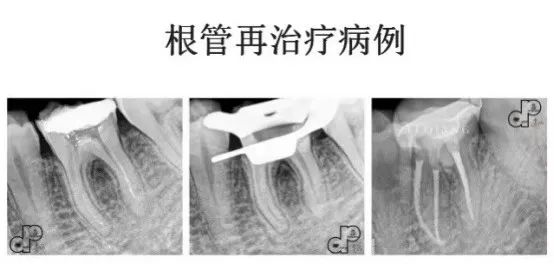

手动锉的探查与疏通 根管长度与根管预备长度的确定 根管预备的宽度确定 根管预备的逐步后退法 根管预备的冠向下法 弯曲根管的预备方法 根管化学预备的常用药物及浓度 化学预备的器械与药物使用步骤 实操:在透明模块和离体牙上实操镍钛锉根管预备

常用根管封药及选择 根管封药与难治性根尖周炎的控制 合适主尖的确定 常用根管糊剂的特性及选择 单尖法根管充填步骤方法 热牙胶垂直加压技术 热牙胶连续波技术 实操:老师在模型上示教单尖法及热牙胶充分步骤方法,学员同步实操。